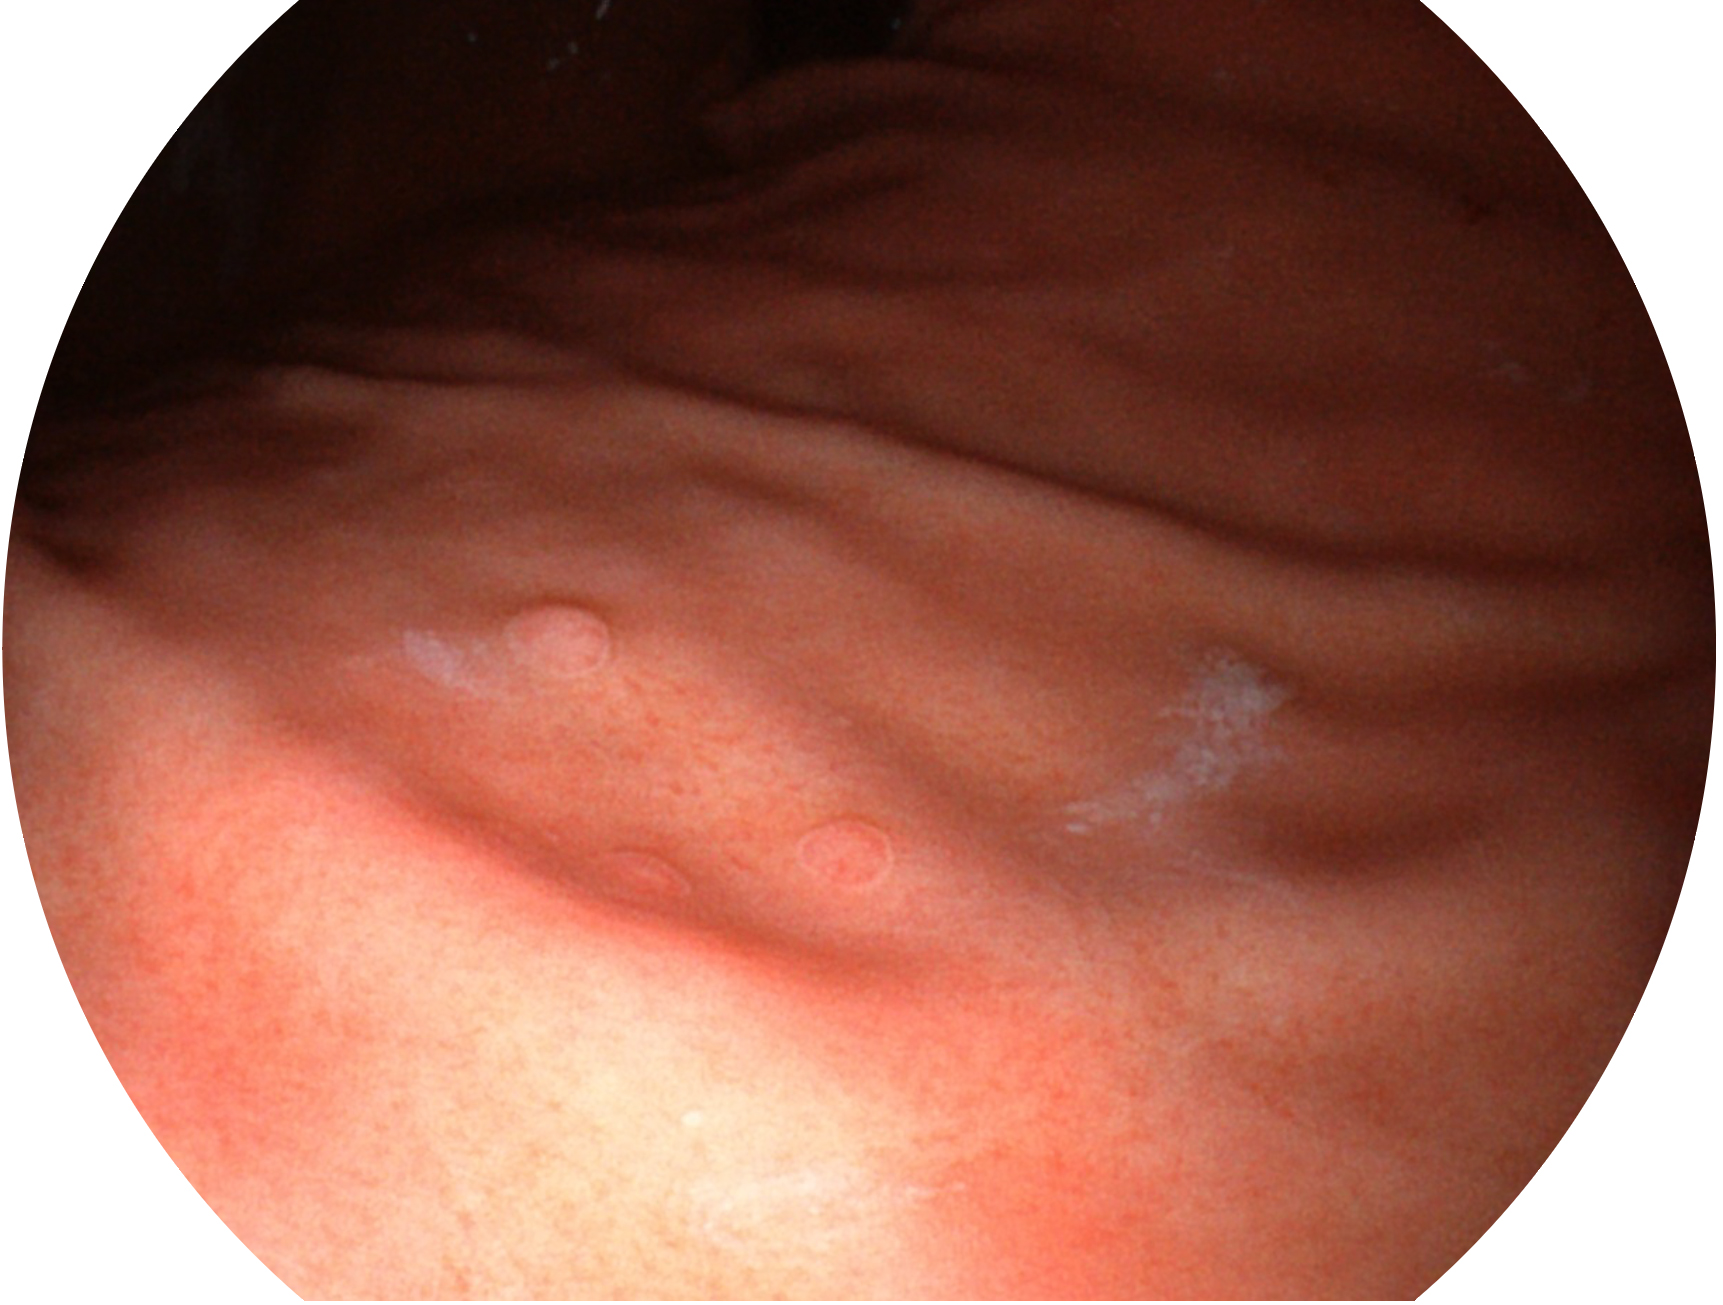

開(kāi)立新開(kāi)發(fā)的內(nèi)鏡染色技術(shù),主要是基于多波長(zhǎng)LED 光源的開(kāi)發(fā),VLS-55Q 四波長(zhǎng)LED 光源是由四個(gè)不同顏色的LED光按照相應(yīng)照明模式所規(guī)定的特定發(fā)光比例進(jìn)行合束后形成,合束后形成的照明光的光譜由紅光、綠光、藍(lán)光及藍(lán)紫光這四個(gè)不同的波段范圍構(gòu)成。具有更高光譜自由度,通過(guò)光譜比例的控制,實(shí)現(xiàn)了聚譜成像技術(shù),英文全稱為“Spectral Focused Imaging, SFI”,縮寫為“SFI”和光電復(fù)合染色成像技術(shù),英文全稱為“Versatile Intelligent Staining Technology, VIST”,縮寫為“VIST”。